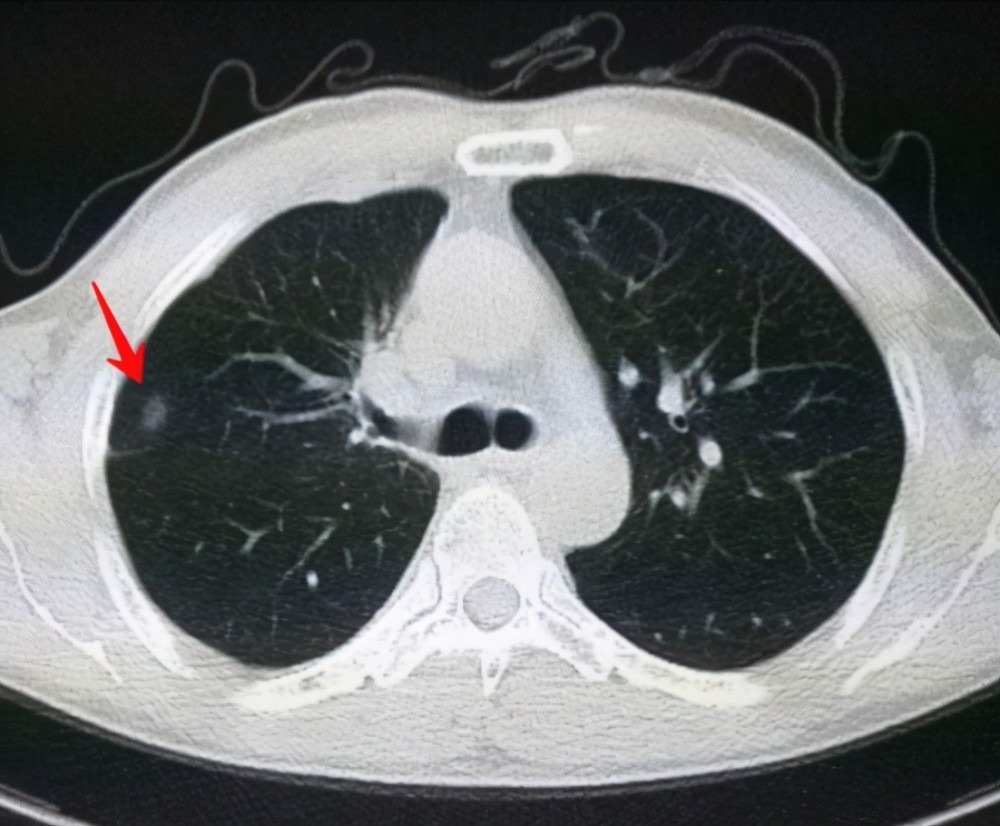

肺結(jié)節(jié)是一種常見的肺部疾病,其發(fā)病率逐年上升,雖然肺結(jié)節(jié)多數(shù)情況下是良性的,但也有可能惡化為肺癌,了解肺結(jié)節(jié)的形成原因?qū)τ陬A(yù)防和治療具有重要意義,本文將為您詳細解析肺結(jié)節(jié)的形成機制。